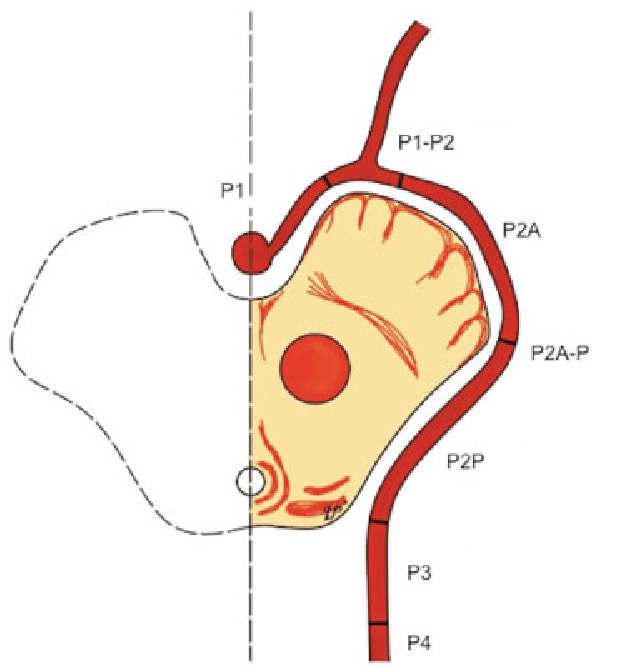

Anatomie vasculaire de l'artère cérébrale postérieure

Source de l'illustration

• P1 : segment pré-communicante

• origine : termination basilaire ;

• terminaison : émergence de l'artère communicante postérieure (PCOM), dans la citerne interpedunculaire ;

• P2 : segment post-communicante

• origine : émergence de l'artère communicante postérieure (PCOM), dans la citerne interpedunculaire ;

• P2A (antérieure) : sous-segment traversant la citerne crurale (en regard des pédoncules cérébraux) ;

• P2P (postérieure ou ambiante) : sous-segment traversant la citerne ambiante jusque dans la citerne quadrigéminale ;

• P3 : segment quadrigéminal

• trajet : postéromedialement au travers de la citerne quadrigéminale ;

• terminaison : entrée dans les sillons du lobe occipital ;

• P4: segment cortical ​

• trajet : dans les sillons du lobe occipital.